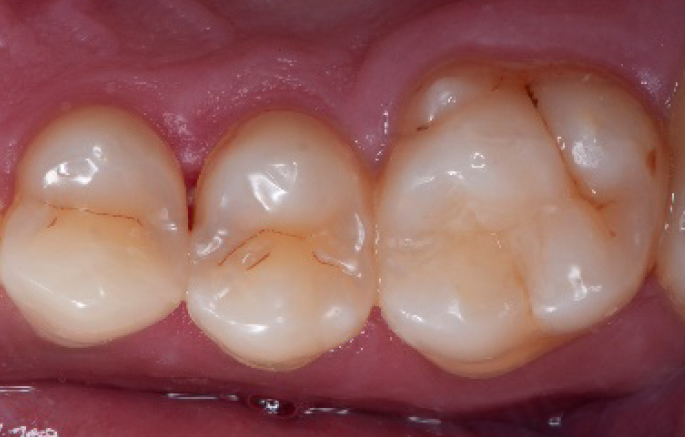

Step 14:

2 weeks control